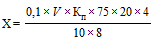

Содержание глицина (X) в мг/мл в препарате вычисляют по формуле:

,

,

где

0,1 - молярность раствора натрия гидроксида;

V - объем 0,1 М раствора натрия гидроксида, израсходованного на титрование, мл;

- поправочный коэффициент к молярности 0,1 М раствора натрия гидроксида;

- поправочный коэффициент к молярности 0,1 М раствора натрия гидроксида;

75 - молярная масса глицина, г/моль;

20 - общий объем смеси (8 мл раствора иммуноглобулина, 7 мл воды и 5 мл кислоты трихлоруксусной 20%), мл;

10 - объем фильтрата, мл;

8 - объем раствора иммуноглобулина, взятого на осаждение, мл;

4 - разведение препарата.